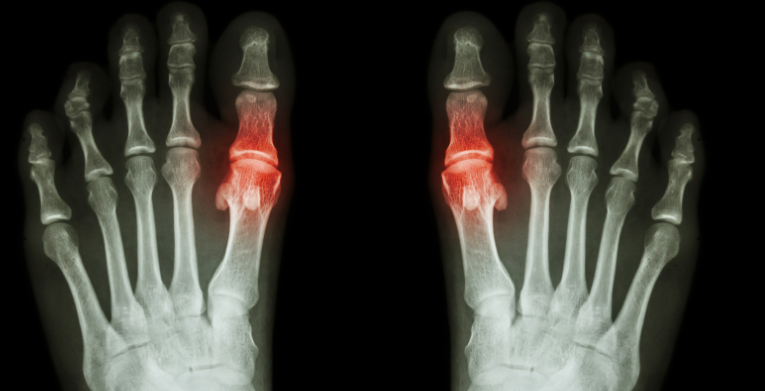

二、芒果与痛风的关系

1. 高嘌呤含量:芒果中的嘌呤含量相对较高。嘌呤是一种在人体内会转化为尿酸的物质,而尿酸是痛风发作的主要原因之一。因此,痛风患者应该控制摄入高嘌呤的食物。